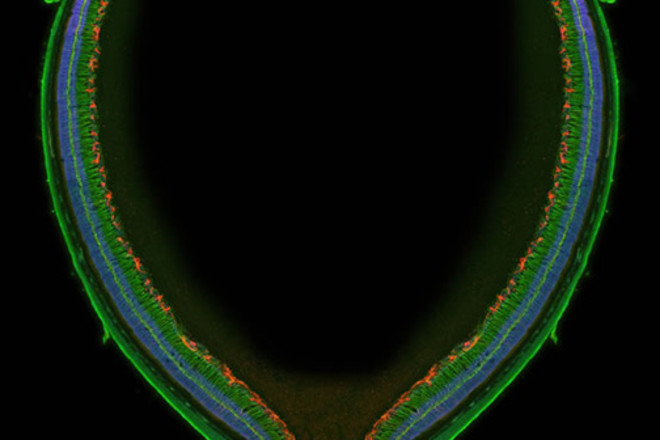

Wellcome Image Awards